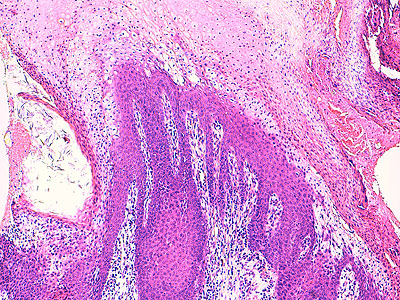

Photo 3 (Hémalun Eosine X 100) : aspect bleu-blanc-rouge à plus fort grossissement,

bleu pour hyperplasie des couches basales, blanc pour vacuolisation des acanthocytes

sous-cornés et rouge pour parakératose de la couche cornée. Le derme superficial est

le siège d’un infiltrat inflammatoire mononucléé périvasculaire modéré.

Légendes de la Photo 3 :

- Flèche bleue pour hyperplasie des couches basales

- Flèche blanche pour vacuolisation des acanthocytes sous-cornés

- Flèche rouge pour parakératose de la couche cornée

- Étoile rouge : Le derme est faiblement à modérément inflammatoire